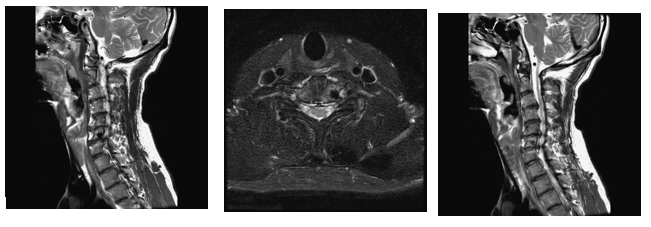

Clinical examination revealed tenderness confined to the neck and upper back, as well as tenderness in the lower back and sacroiliac joints. Cervical rightward rotation and left shoulder elevation were restricted. Laboratory tests showed a mildly elevated eosinophil count (8.0%). Imaging studies, including cervical spine AP and lateral X-rays, demonstrated C5-C7 intervertebral space narrowing and retrolisthesis. Tc-99m methylene disphosphonate (MDP) whole body bone scan with whole-body imaging was arranged, and localized imaging with single-photon emission computed tomography (SPECT)-CT for cervical-thoracic spines confirmed increased radiotracer uptake in the C6 vertebra, identifying a 0.7 cm cystic lesion (Figure 1). On T1-weighted images, the intervertebral disc was clearly seen herniating into the C6 vertebra, with the herniated portion connecting to the cavitated lesion (Figure 2A). Another image (Figure 2B) demonstrated the C7 vertebra compressing the intervertebral disc upward, causing partial rupture. On T2-weighted images, the cavity appeared hypointense (Figure 3A & 3B), and a distinct ring of sclerosis surrounds the cavity (Figure 3B), which is characteristic of Schmorl's cyst.4 Based on axial images (Figure 3C), it is suggested possible prior communication with cerebrospinal fluid. Furthermore, degenerative disc disease (DDD) was noted at C3-C4 and C4-C5, while C5-C6 and C6-C7 showed DDD with grade I retrolisthesis.

Figure 3 On T2-weighted images, the cavity appeared hypointense (Figure 3A, B), and a distinct ring of sclerosis surrounds the cavity (Figure 3B). On (Figure 3C) images suggested possible prior communication with cerebrospinal fluid..

In view of radiologic evaluation, proper image provided critical insights into the pathology. X-ray imaging revealed that the vertebral contour remained intact, with no evidence of aggressive bone destruction (not shown). On the bone scan, there was increased radiotracer uptake in the C6 vertebra (Figure 1), consistent with the first scintigraphic findings in Schmorl’s node.5 MRI images showed the intervertebral disc herniating into the C6 vertebra, with the herniated portion connecting to the cavitated lesion (Figure 2A & 2B), and the C7 vertebra compressing the intervertebral disc upward, causing partial rupture. Also, the cavity of C6 appeared hypointense (Figure 3A & 3B), with a distinct ring of sclerosis surrounds the cavity (Figure 3B), which is characteristic of Schmorl's cyst.4 MRI findings further clarified the pathology of Schmorl’s node, which typically appears a small bony notch filled with herniated disc material in the upper or lower endplate of a vertebral body.6

With respect to differential diagnoses for spinal cysts or cavities, the pathology of simple bone cyst (SBC), aneurysmal bone cyst (ABC), brown tumor, infection, and giant cell tumor should be considered. For SBC and ABC, both lesions typically exhibit high T2 signal intensity due to their fluid content.7 However, SBCs arise within the bone and do not exhibit features of nucleus pulposus of intravertebral hernia, as clearly observed in Fig. A. On the other hand, ABCs often have a multilobulated contour and demonstrate fluid-fluid levels on imaging,8,9 features that are not observed in this case. Regarding brown tumor and giant cell tumor, these lesions frequently cause expansible bone destruction and mass effects, and demonstrate fluid levels or internal septations.10–13 However, the MRI findings in our case showed no signal enhancement, effectively excluding these neoplastic lesions. For infection, infectious lesions typically present with surrounding soft tissue edema and T2 hyperintensity.14–16 In this case, these features were not present, and clinical data did not support infection. Although SPECT-CT revealed increased radiotracer uptake, there were no additional findings to suggest an infectious process, which was not considered as well.